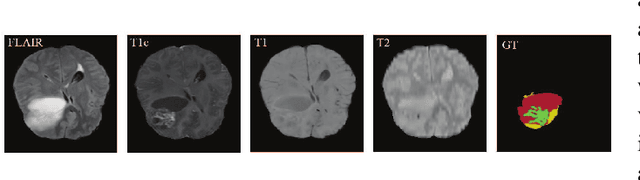

In the field of multimodal segmentation, the correlation between different modalities can be considered for improving the segmentation results. In this paper, we propose a multi-modality segmentation network with a correlation constraint. Our network includes N model-independent encoding paths with N image sources, a correlation constraint block, a feature fusion block, and a decoding path. The model independent encoding path can capture modality-specific features from the N modalities. Since there exists a strong correlation between different modalities, we first propose a linear correlation block to learn the correlation between modalities, then a loss function is used to guide the network to learn the correlated features based on the linear correlation block. This block forces the network to learn the latent correlated features which are more relevant for segmentation. Considering that not all the features extracted from the encoders are useful for segmentation, we propose to use dual attention based fusion block to recalibrate the features along the modality and spatial paths, which can suppress less informative features and emphasize the useful ones. The fused feature representation is finally projected by the decoder to obtain the segmentation result. Our experiment results tested on BraTS-2018 dataset for brain tumor segmentation demonstrate the effectiveness of our proposed method.